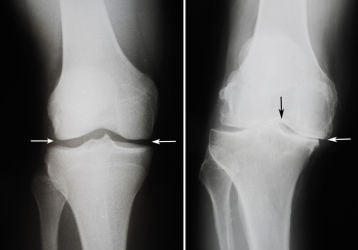

Деформирующий артроз коленного сустава 1, 2, 3 степени: причины, симптомы, лечение

Что представляет собой деформирующий артроз коленного сустава, по каким причинам появляется заболевание. Симптомы и признаки, лечение 1,2,3 стадий.